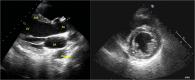

Dengue fever is a mosquito-borne arthropod-borne viral (arboviral) tropical disease in humans affecting 50-528 million people worldwide. The acute abdominal complications of dengue fever are acute appendicitis, acute pancreatitis, acute acalculous cholecystitis and non-specific peritonitis. Acute pancreatitis with new onset diabetes in dengue shock syndrome (DSS) is very rarely reported. We describe a case of 30-year-old man admitted in intensive care unit and was diagnosed with DSS with RT-PCR, NS1 antigen and dengue IgM antibody being positive. Abdominal ultrasound and computerized tomography confirmed acute pancreatitis. Patient required insulin after recovery. Diabetes mellitus caused by DSS is under-reported and lack of awareness may increase mortality and morbidity.